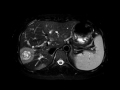

Hepatic Epithelioid Hemangioendothelioma (EHE)

MRI images demonstrate multiple peripheral lesions throughout the liver many of which appear confluent, and the largest of which demonstrates a "ring" morphology on T2 and post-gadolinium sequences, a characteristic pattern for hepatic epithelioid hemangioendothelioma